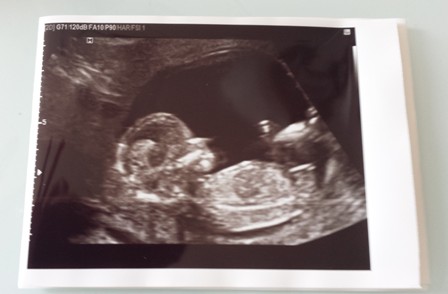

Ze heeft een koppie met veel en héél donker haar, is kleiner dan haar grote zus, maar lijkt er voor de rest toch wel een beetje op. En dan heb ik 't over onze nieuwe spruit: Nicole Juliëtte. Want ja hoor, daar was ze dan eindelijk. Het was het wachten wel waard. … [Read more...] about En ja hoor, daar was ze!